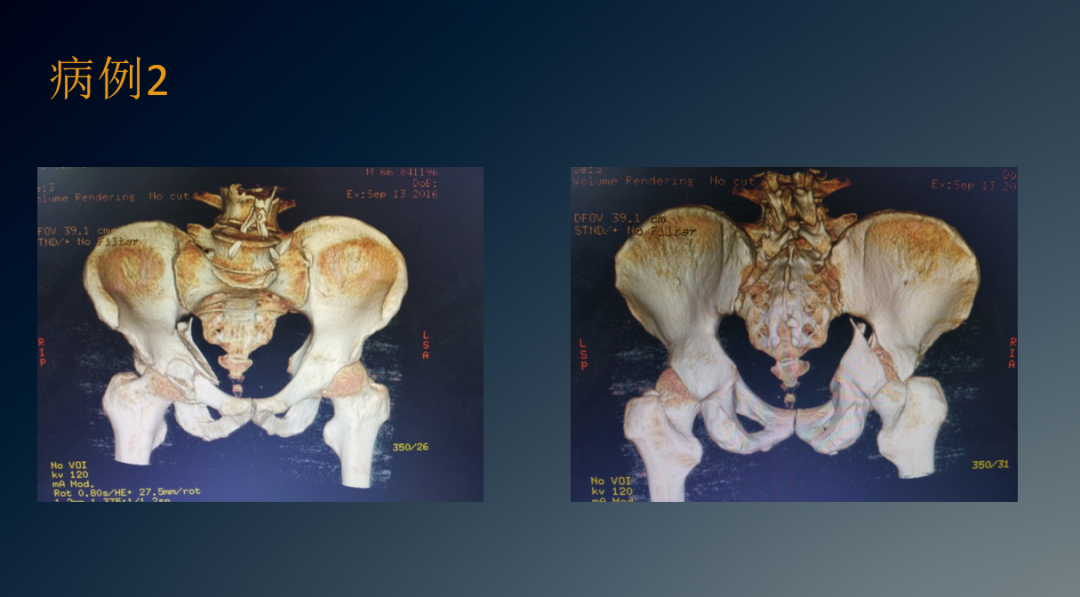

临床病例

治疗盆骨、髋臼骨折常用的手术入路有髂腹股沟入路、K-L入路,前后联合入路,扩大的髂股入路等。髂腹股沟入路主要用于髋臼前壁和前柱骨折,但对于双柱骨折、后壁骨折或累及骶髂关节的髂臼骨折,不建议使用此入路。

K-L入路可直视髋臼后柱的全部侧面,适用于移动的髋臼后柱骨折。扩大的髂股入路对髋臼前柱、关节囊和坐骨大切迹的显露良好,尤其是可显露髋臼顶部的骨折,但因要兼顾前后柱,切口较大,要将臀肌从髂骨上剥离,损伤大出血多。前采用该入路术后出现异位骨化的几率高达85.7%。

因此,该入路目前以较少使用。前后联合入路即K-L入路联合髂腹股沟入路,通过K-L入路可经坐骨小切迹观察四边形区及后柱的骨折复位情况,通过髂腹股沟入路可显露骶髂关节前方,髂骨翼,无名骨,前柱及耻骨联合。采用前后联合入路可减少单一切口所致切口大、肌肉剥离广泛,易损伤血管神经等弊端,可明显减少对髂关节后方组织的干扰,降低异位骨化的发生几率。